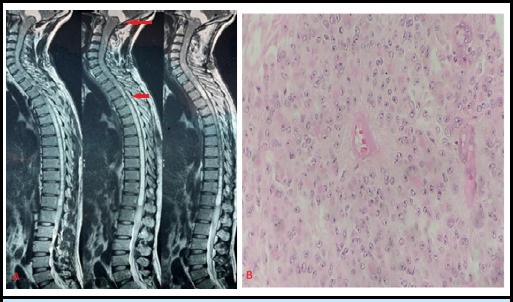

Spinal cord tumors, though uncommon, pose significant challenges due to their potential for neurological disability and mortality. Intramedullary spinal cord tumors, particularly Long-level intramedullary spinal cord tumors, present challenging clinical scenarios. Contrast-enhanced Magnetic resonance imaging remains pivotal for radiological evaluation and surgical planning. Notably, aggressive resection is advocated to enhance prognosis, with meticulous attention to preserving neurological function. Advancements in spinal surgery techniques, coupled with intraoperative monitoring, offer promising avenues for improved patient outcomes. We presented three cases of long-level intramedullary tumors, emphasizing the significance of tailored management and presented details, including clinical presentations, radiological findings, and histopathological results.

Abstract Image